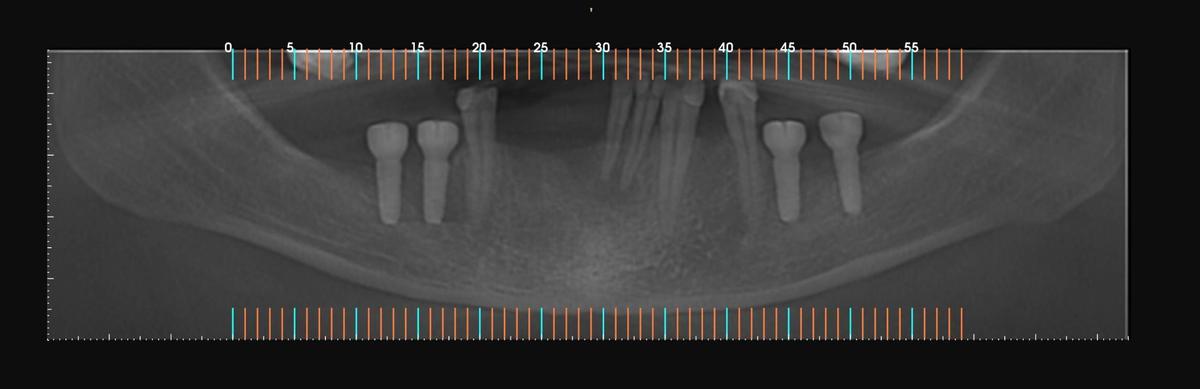

PRÓTESE TOTAL FIXA EM IMPLANTES

M.A.S.L.